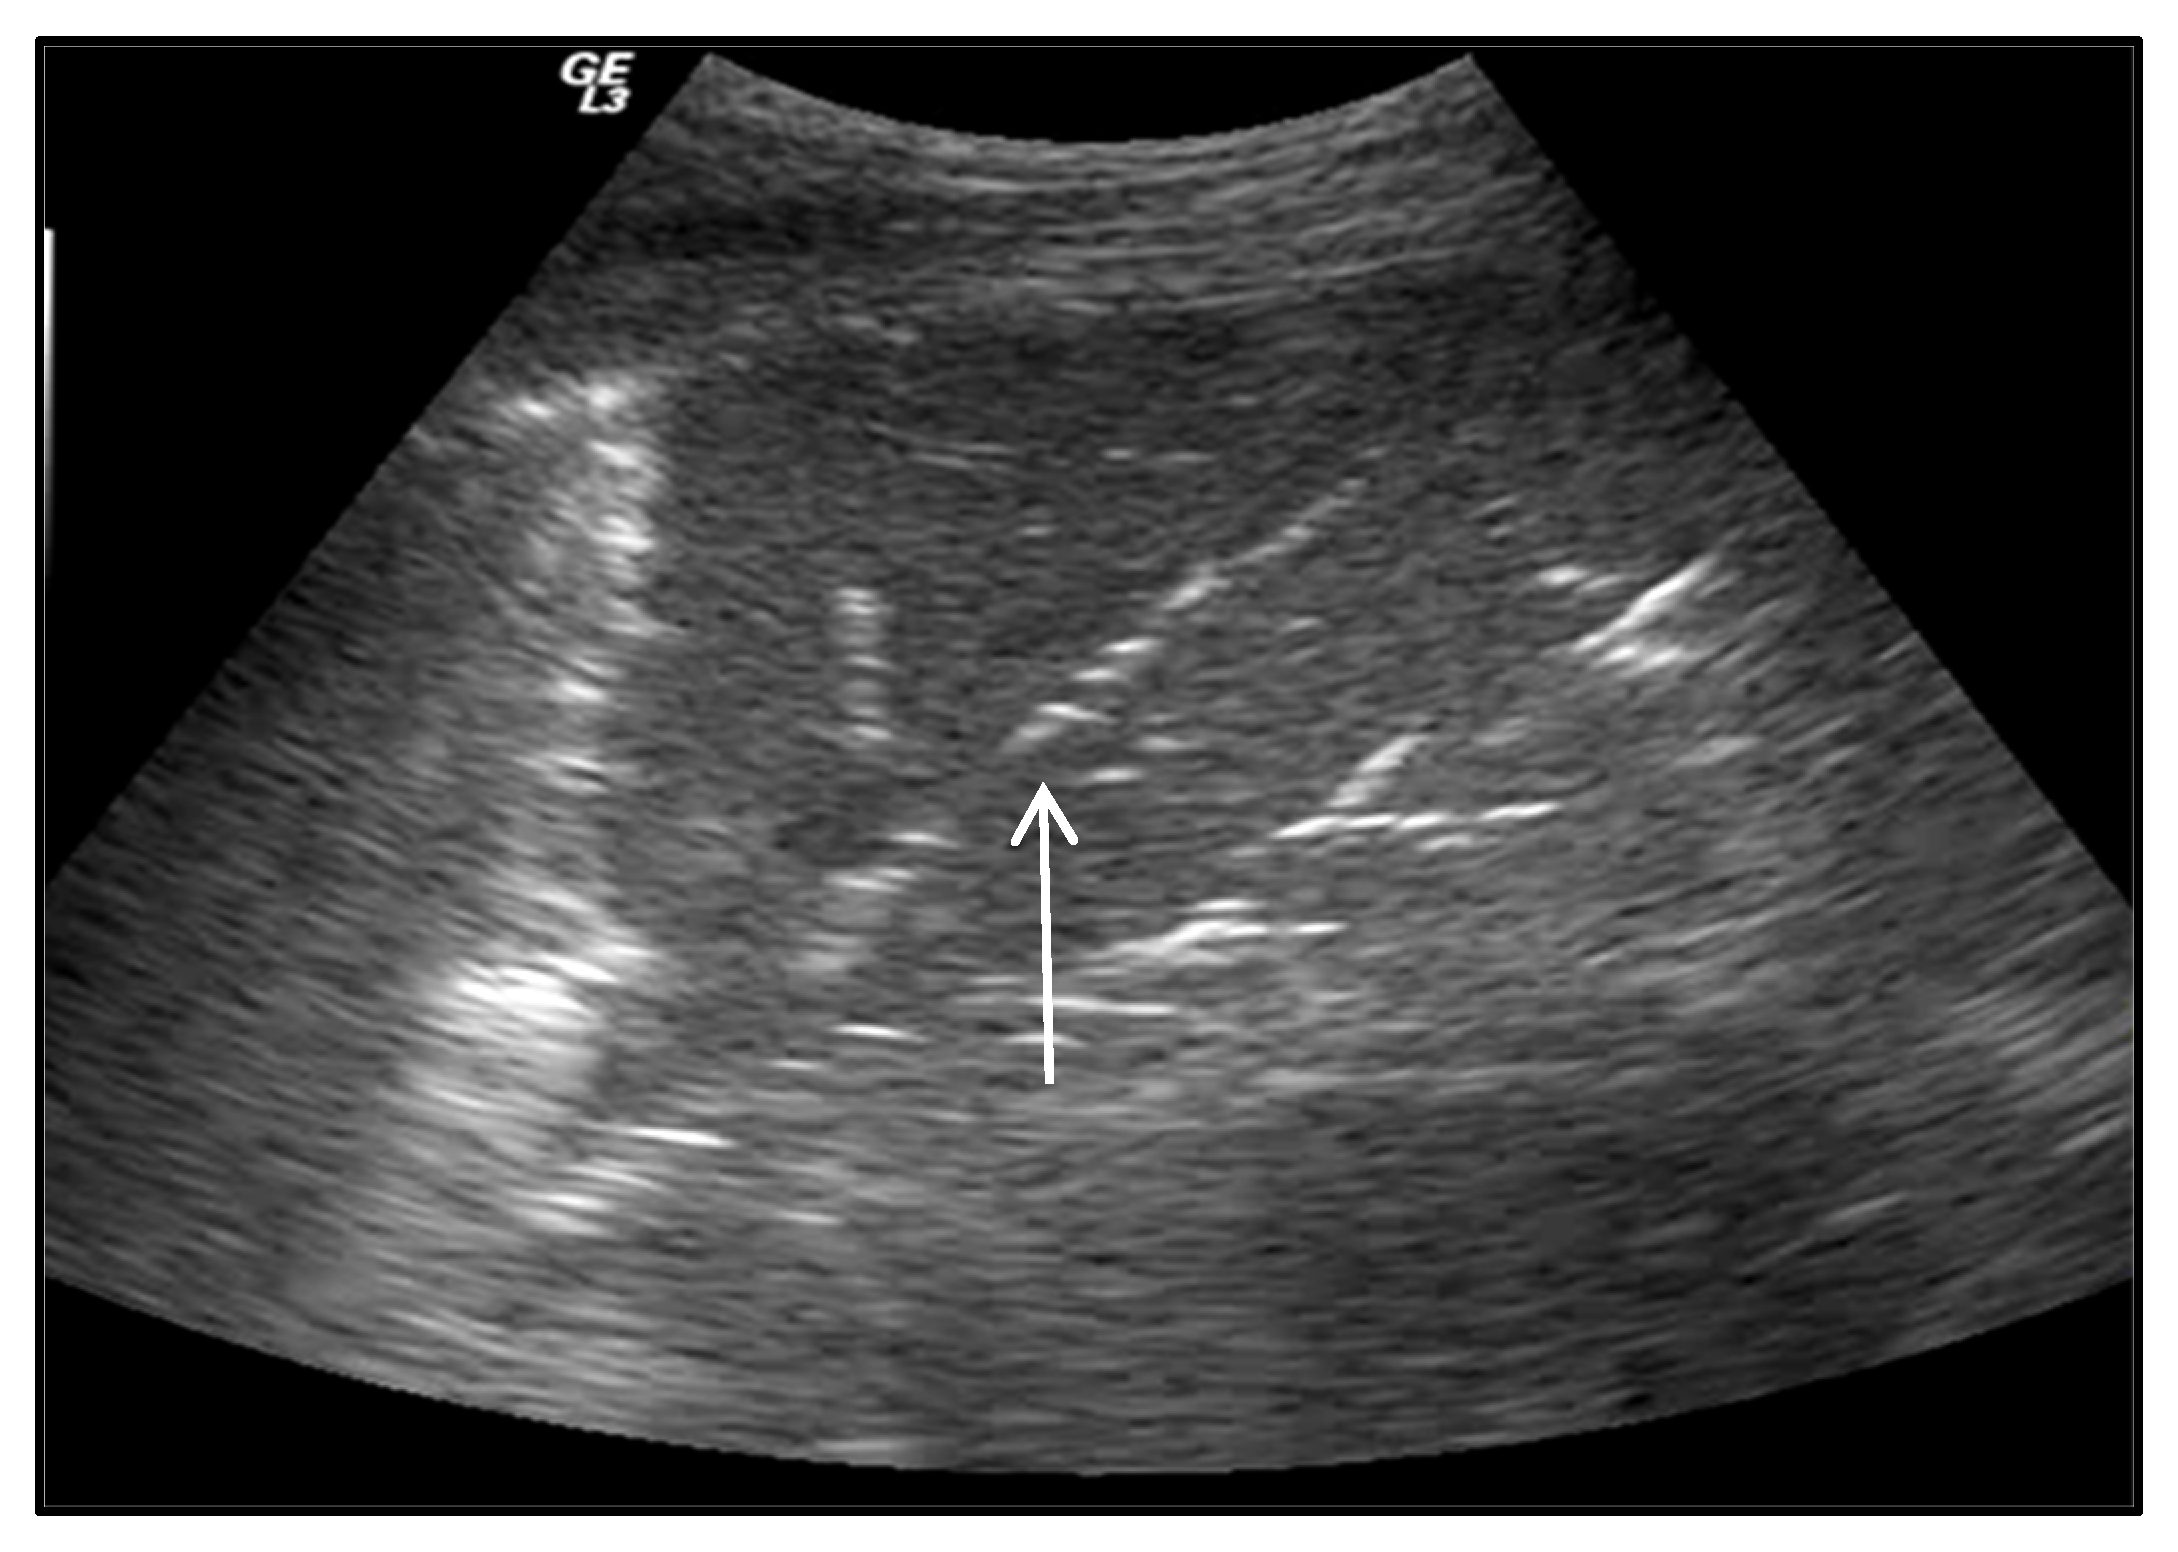

2.3.2. Lung Consolidation

2.3.3. Pulmonary Embolism